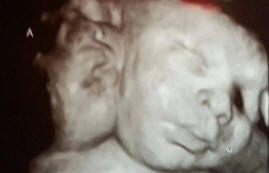

Ilyen gyermekek – egy millióból, a gyermeknek kettője van egyedül működő fejek, de egy test és egy szív, és a szülők nagyon örülök, hogy feltöltik a családot.

Asa és Ali Hamley Robin harminckét szülője lett és Michelle. Az orvostudomány nyelvén eltérésüket dicefálisnak nevezik parapagus, vagyis az ikrek állapota, amikor az összes szerv túl van kivéve a célokat, közös.

Ez az eset érdekes, mert általában az ilyen gyermekek nem maradnak túl. Ezer esetben egy nő teherbe eshet ilyen gyermekkel, millió embernél csak egy kétfejű gyermek sikerül túlélni.

Asa-nak és Eli-nek három tüdeje van, kivéve a könnyed tüneteket szívzavarok, testük rendben van.